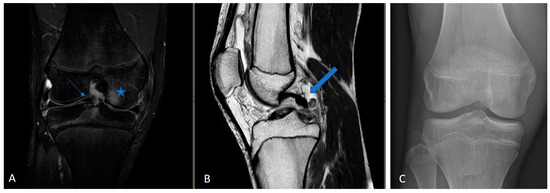

A high rate of favorable functional outcomes was observed, with a mean subjective IKDC score of 91.8 ± 7.2, Lysholm score of 96.6 ± 7.9, and KOOS score of 94.2 ± 5.3. Additionally, knee stability assessments indicated a mean side-to-side difference of 2.2 ± 1.5 mm in KT-1000 testing, with no significant difference between patients undergoing primary versus revision ACL reconstruction (Figure 3).

Figure 3.

Visualization of the distribution of IKDC, Lysholm, and KOOS scores, showing predominantly good to very good results. While the IKDC score displays some variability, the Lysholm and KOOS scores are more consistently clustered near the upper range.